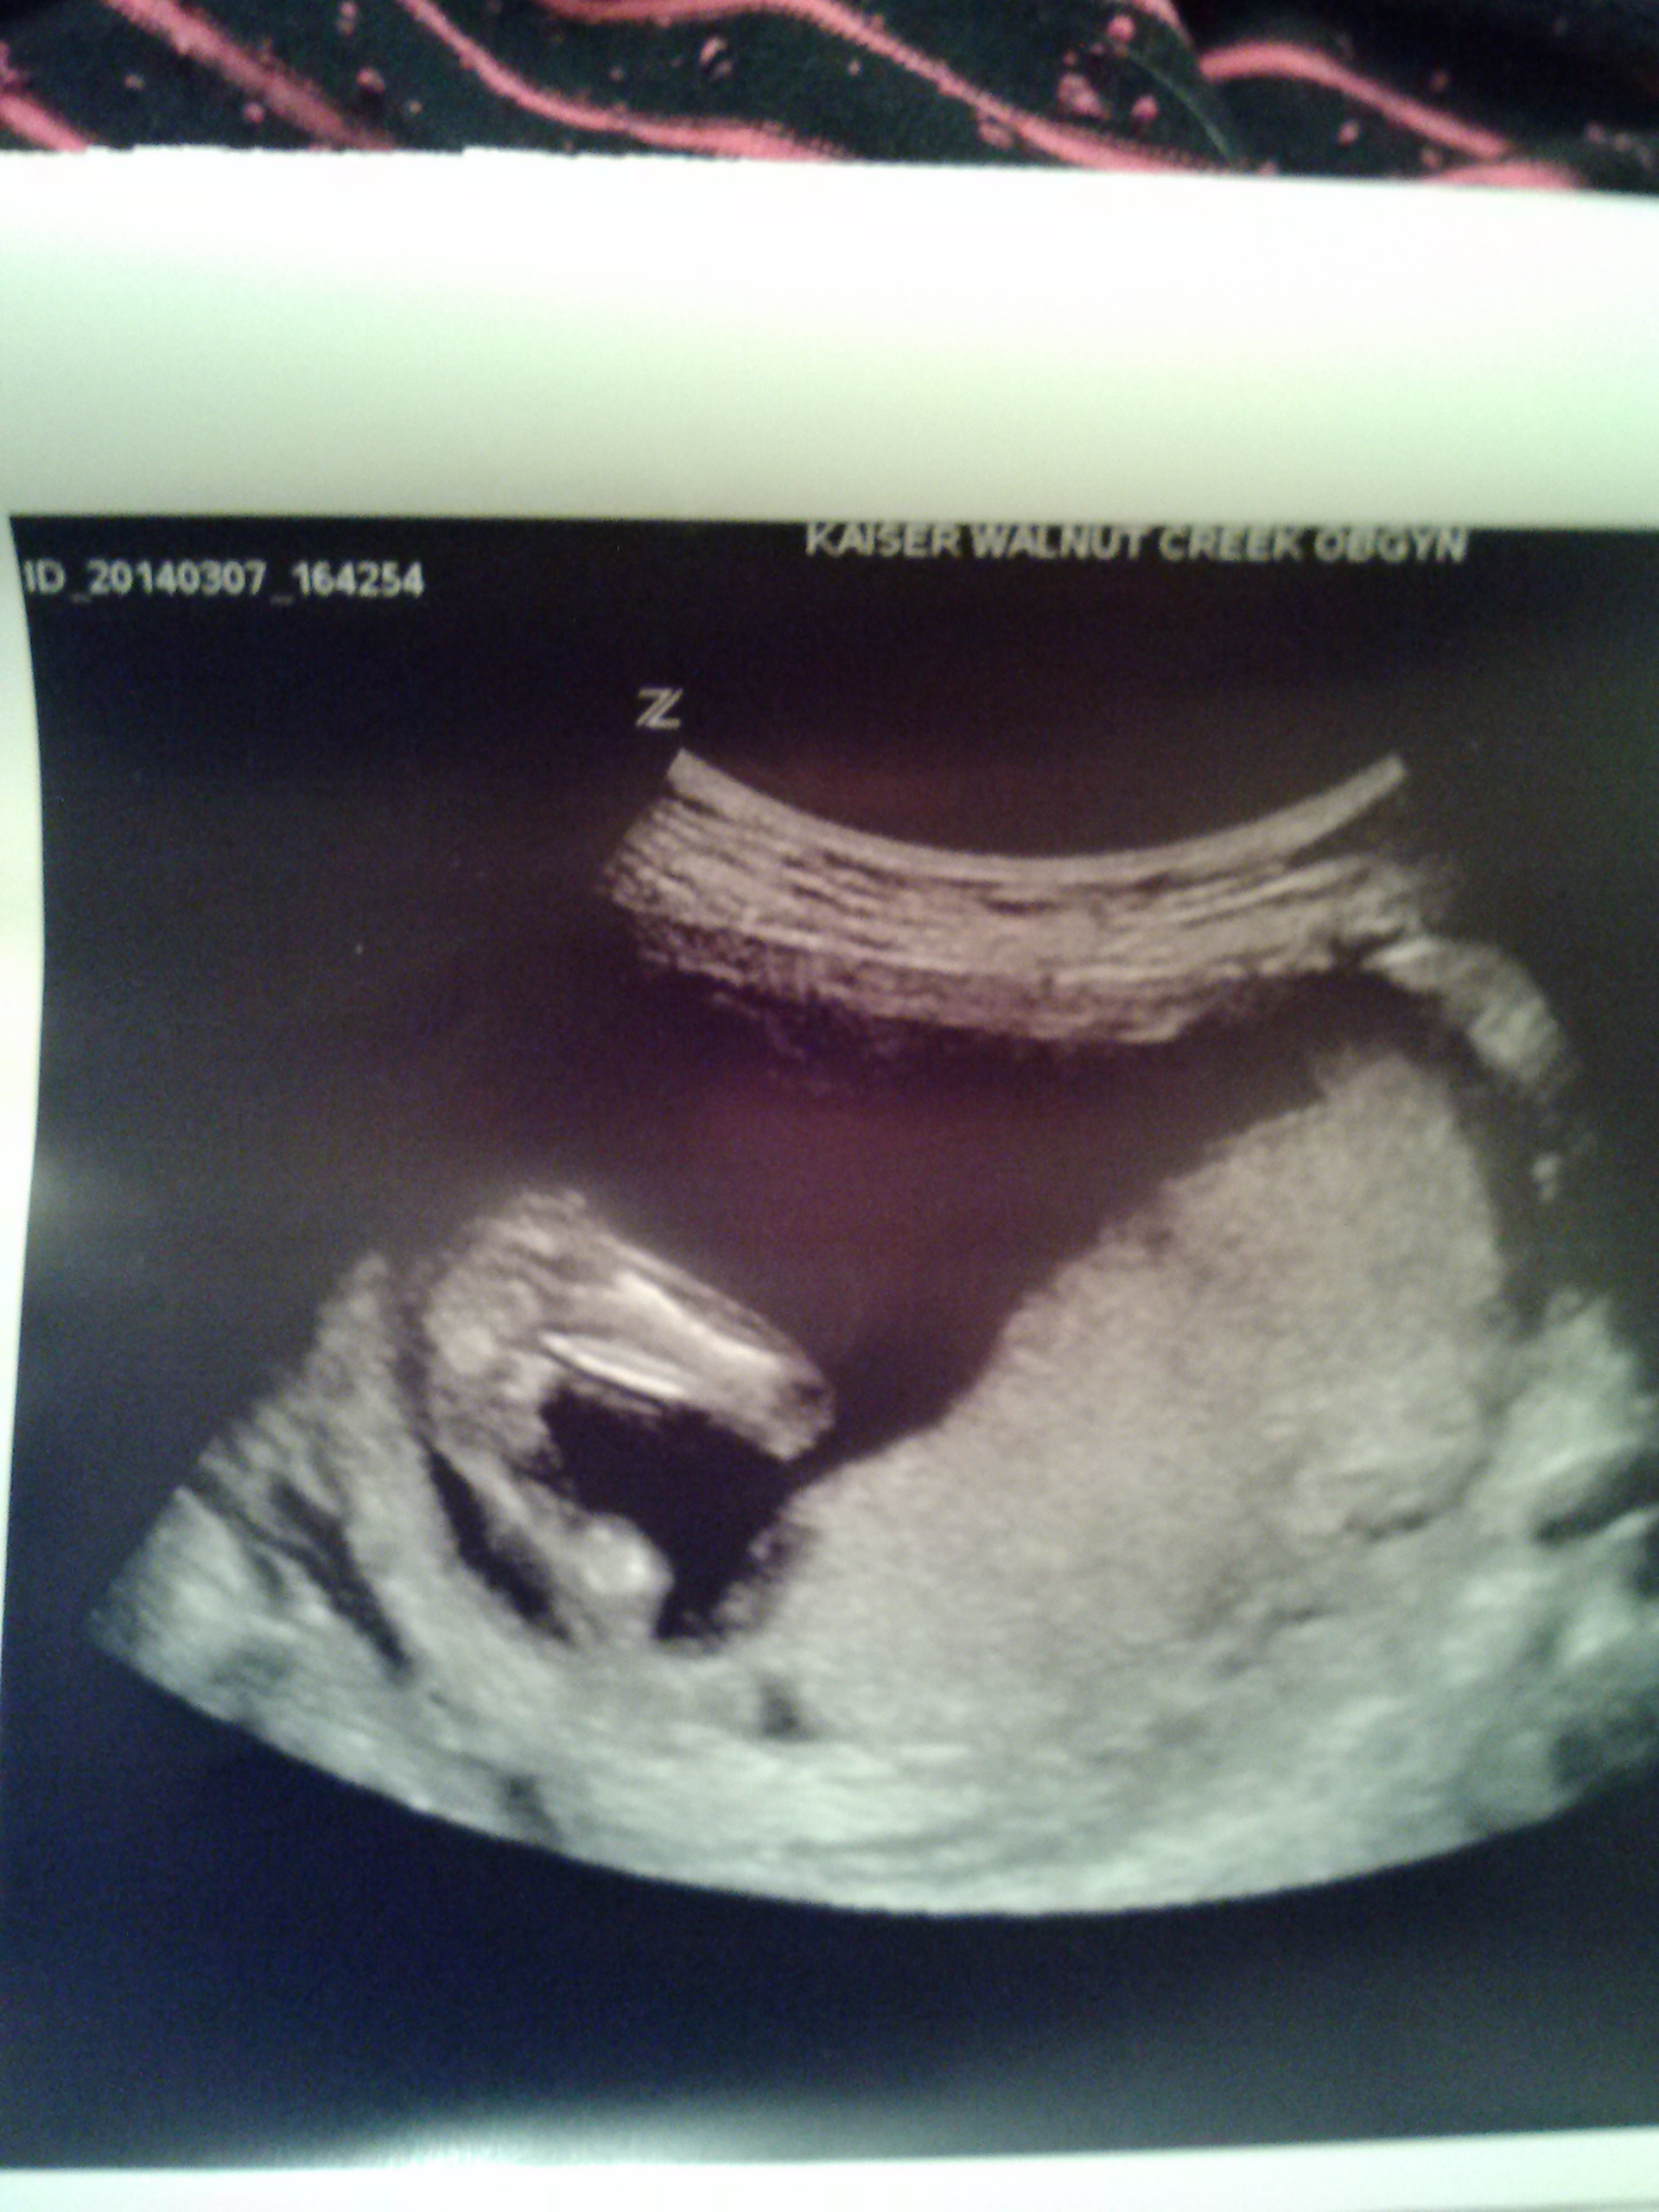

I posted another post of a profile shot at 12 weeks and 6 days.....here it is again....what about this one??? Thanks!!Attachment 17689

boy I think xx

I would say the nub looks boy and the potty looks girl...I'd go with the nub

I think girl